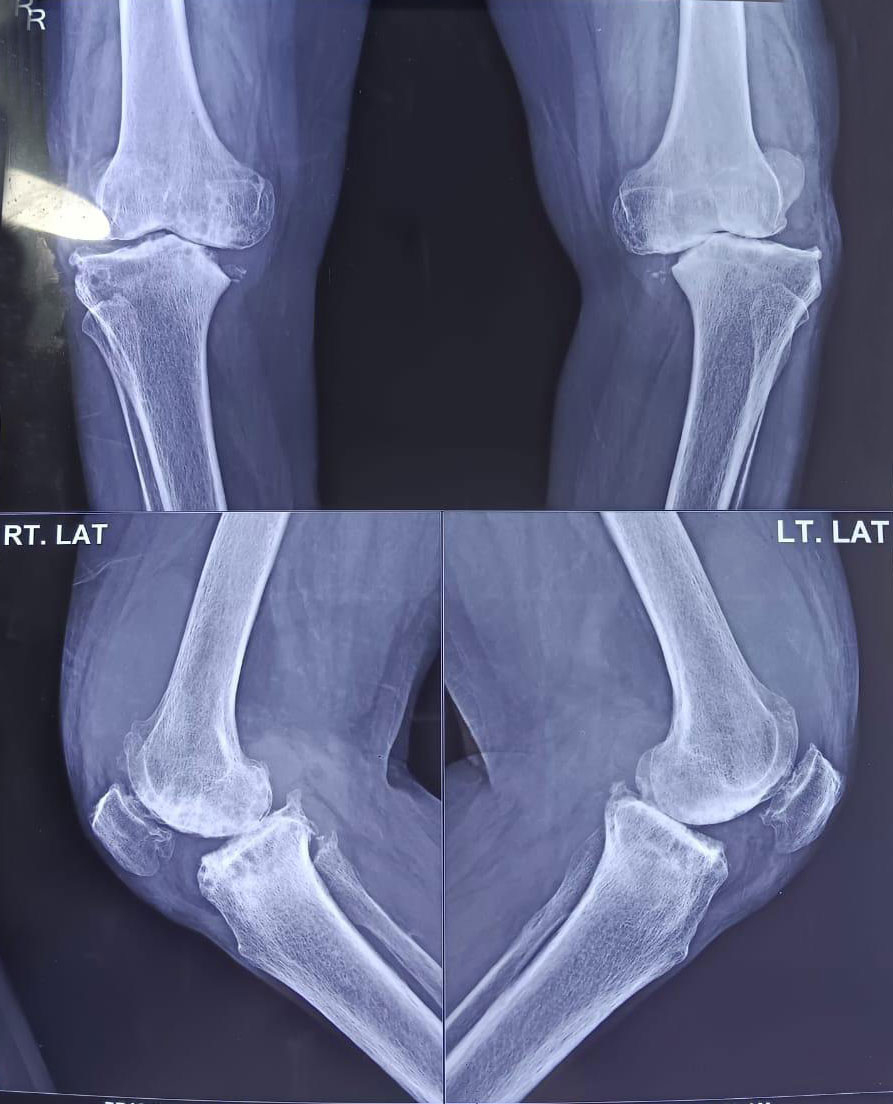

Total knee replacement, also called total knee arthroplasty, is a surgical procedure in which the worn out or damaged surfaces of the knee joint are removed and replaced with an artificial prosthesis.

Indications for Total Knee Replacement

Total knee replacement surgery is commonly indicated for severe osteoarthritis of the knee. Osteoarthritis is a type of arthritis. It is the most common form of knee arthritis in which the joint cartilage gradually wears away, and often affects the elderly. Your doctor may advise total knee replacement if you have: